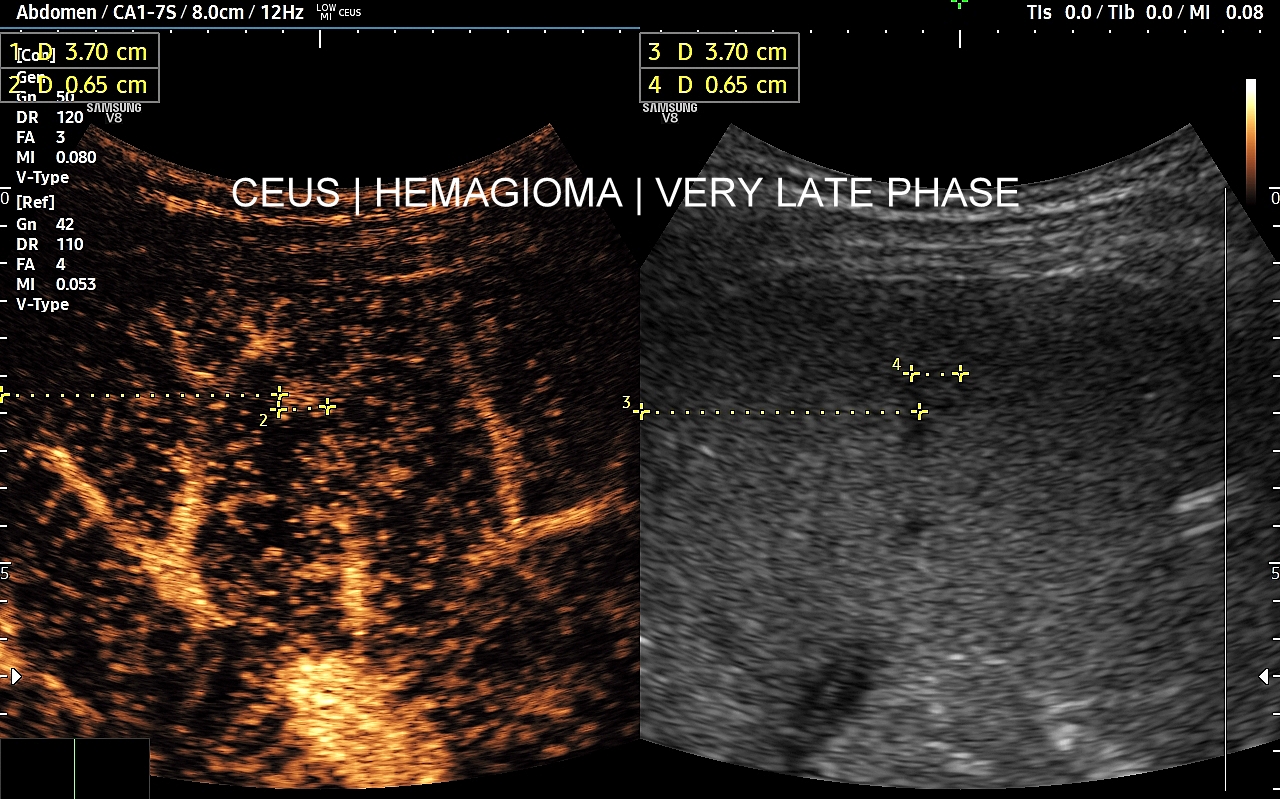

Najbardziej charakterystyczną cechą naczyniaka wątroby w badaniu CEUS jest jego wypełnianie w postaci guzkowej (ang. peripheral nodular enhancement) od obwodu ku centrum zmiany (ang. centripetal). Szybkość wypełniania bywa różnorodna, może być powolna lub szybka. W przypadku szybkiego wypełniania (tzw. flash-filling), w celu wykazania charakterystycznego centrypetalnego wypełniania niezbędna może być postprocessing’owa analiza poklatkowa zapisanego nagrania badania. W fazie późnej naczyniak wątroby pozostaje izowzmocniony lub hyperwzmocniony w stosunku do natywnego miąższu wątroby.

W przypadku dużych naczyniaków obszary, które uległy wykrzepianiu pozostają awaskularne przez wszystkie fazy badania CEUS, tj. nie wypełniają się kontrastem (nonenhancing). W przeciwieństwie do powyższego konstelacja, w której to w fazie wczesnej pojawia się wzmocnienie, a następnie w fazie wrotnej lub późnej ulega wypłukaniu (hypoenhancement) świadczy o cechach złośliwych diagnozowanej zmiany ogniskowej w wątrobie i wyklucza rozpoznanie naczyniaka.

W razie braku pewności co do wypełnienia guzka w stosunku do natywnego miąższu wątroby, tj. słabo dostrzegalnych wizualnie różnic, pomocne może być wykorzystanie w ramach obróbki postprocessing’owej ilościowej oceny wypełnienia kontrastem poszczególnych obszarów, tj. guzka i prawidłowego miąższu, w ramach analizy TIC (ang. time intensity curve). Metoda ta polega na umieszczeniu jednego znacznika w zmianie ogniskowej, drugiego w kolejnym obszarze, a następnie porównania ich obu pod kątem intensywności sygnału na osi czasu.